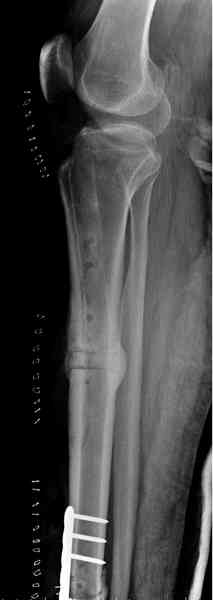

Недавно на нашей ежемесячной Morbidity&Mortality

conference мы разбирали похожий случай, ложный сустав большеберцовой кости после резекции опухоли.

К нашему онкологу-ортопеду обратился больной с жалобами на боли в голени, из рассказа - год назад была сделана биопсия большеберцовой кости, но название заболевания "не запомнил”.

Оперирован в военном госпитале с заменой сегмента

аллокостью большеберцовой кости и после демобилизации явился для постоянного наблюдения по месту жительства.

В литературе "A Classic Adamantinoma Arising from

Osteofibrous Displasialike Adamantinoma in the Lower Leg: A case report and Review of the Literature похожие снимки.

Наши имели проблему со сращением, пришлось им сделать динамизацию, дополнительную аутопластику.

Снимки представлены.